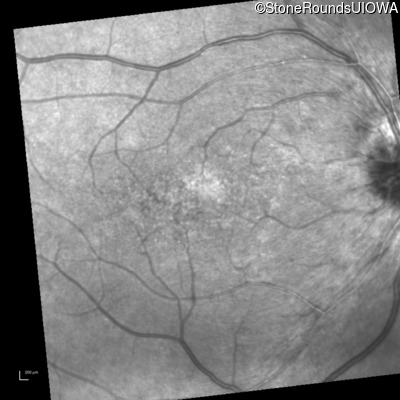

Infrared Fundus Photograph - Right - 20/30 -2

Exemplar